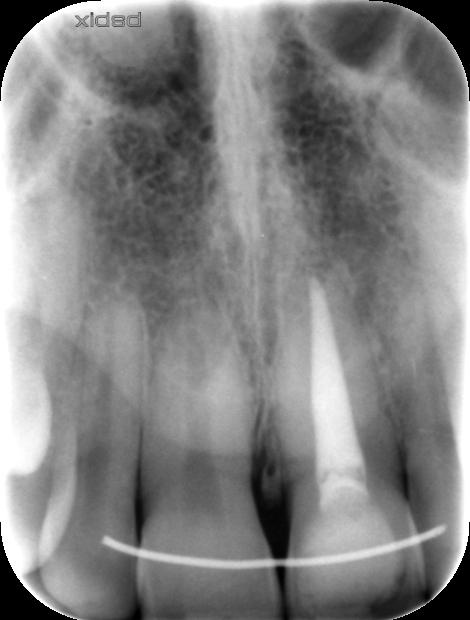

Un ancien traitement de racine est présent sur l'incisive gauche

Il a coloré la base de la dent

2) Lorsque la décoloration est plus profonde, qu'elle est due par exemple à un traitement de racine, il est possible de blanchir la dent depuis l'intérieur. On parle de blanchiment interne.

Une petite cavité est faite à l'arrière de la dent, un produit à base d'eau oxygénée est déposé à l'intérieur et laissé en place quelques semaines.

Il faut répéter la séance 2 ou 3 fois. Puis la dent est rebouchée de façon hermétique avec un composite.